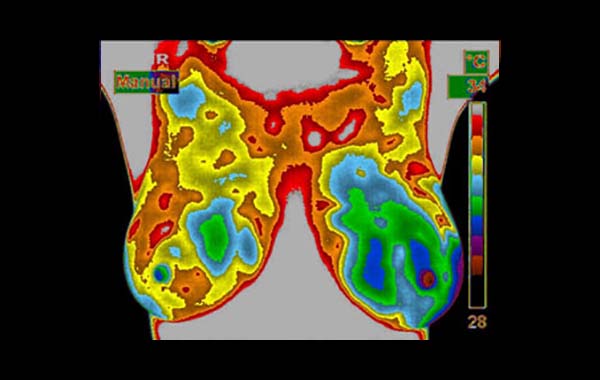

What is the doctor looking for when he interprets the scans?

The doctor is analyzing the breasts for 22 different vascular and thermal factors. The simplest of which is comparing one breast to the other looking for blood vessel and heat asymmetries. Once detected and analyzed, each breast is graded and classified into one of five TH (Thermo-biological) levels.